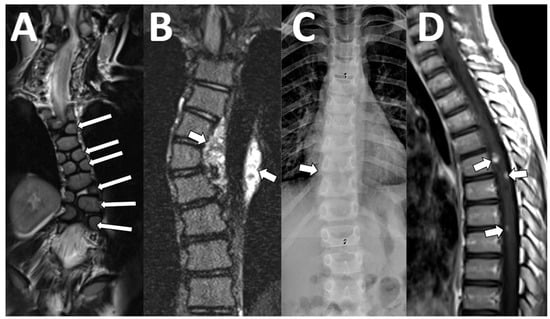

Imaging signs of spinal leptomeningeal disease include abnormal leptomeningeal enhancement and/or extramedullary nodules, which may or may not be enhancing. Our MRI protocol includes two 3D sequences, one post-contrast 3D T1-weighted sequence to assess for enhancing lesions [16], and one heavily T2-weighted to detect small nodular leptomeningeal disease that may not be enhancing [17] (Table 1) (Figure 3). Primary brain tumors that are diffusion-restricting can benefit from the addition of spine diffusion to detect non-enhancing cellular metastatic lesions on spine surveillance MR imaging [13].

Figure 3. Spinal metastatic disease. An 8-year-old male with a newly diagnosed thoracic intramedullary tumor that was determined to be an ependymoma on subsequent surgical pathology. The conventional sagittal T1-weighted images show some inhomogeneous signals in the thecal sac ((A) arrow), with subtle contrast enhancement on sagittal T1-weighted imaging ((B) arrow). The sagittal 3D T2 acquisition shows definite soft tissue ((C) arrow) with increased diffusion ((D), arrow) and diffusion restriction ((E), arrow), consistent with metastatic disease.